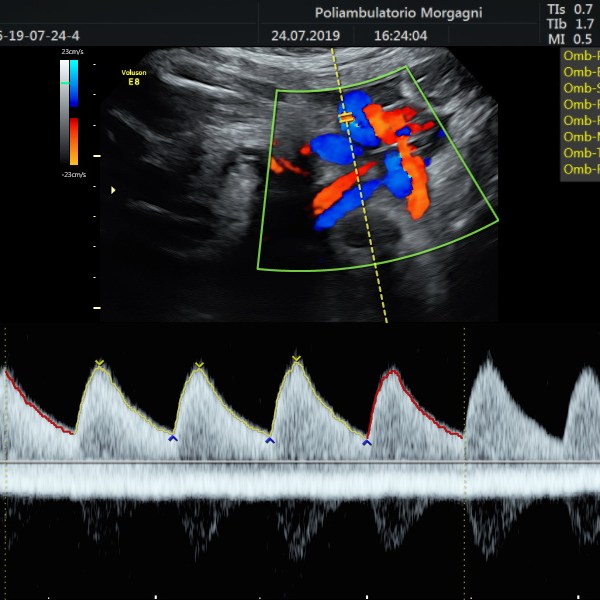

Il mese si conclude con l’ecografia di accrescimento da non eseguire troppo precocemente per ridurre il lasso di tempo fino al momento del parto.

Oltre la valutazione della biometria fetale, è importante controllare il benessere fetale con flussimetria a livello del cordone ombelicale e la quantità di liquido amniotico, vera cartina di tornasole del benessere fetale.